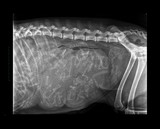

Radiographie